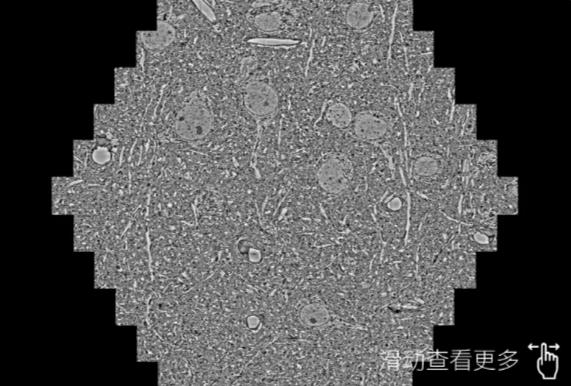

鼠脑切片。左图使用长治蔡司长治扫描电镜MultiSEM706对165μmx143pm面积区域成像,耗时仅需1.5秒。右图为鼠脑切片中30μm区域放大效果。样品由芝加哥大学B.Kasthuri提供。

使用蔡司高速长治扫描电镜MultiSEM对1mm²人脑皮层组织进行高分辨成像,并对其中的各种细胞结构进行三维重构分析。左图展示了2x3mm²组织平面中锥体神经元的三维重构效果。右图显示了局部体积神经元三维重构。图像由哈佛大学chtman实验室提供,渲染图由D. Berger 制作。